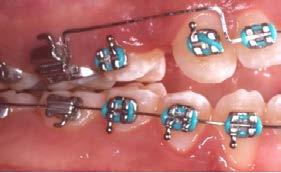

Caso clínico: paciente femenino de 19 años, patrón dolicofacial, perfil convexo, clase II esqueletal debido a una retrusión mandibular, mordida abierta anterior esqueletal, clase II molar, clase canina no establecida por mordida abierta, apiñamiento severo superior e inferior y deglución atípica.

Resultados: obtención de una clase canina I y clase molar II funcional, se corrigieron las sobremordidas horizontal y vertical, y se logró la coincidencia de líneas medias facial y dental. El manejo de la mordida abierta anterior se llevó a cabo por medio de la corrección del hábito de deglución atípica con la ayuda de spikes de resina, elásticos intermaxilares y arcos utility, y se obtuvieron buenos resultados estéticos, dentales y funcionales.